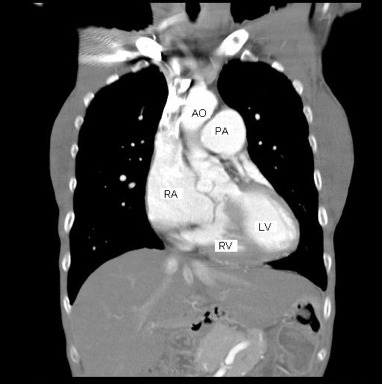

図4: 造影CT検査、大動脈騎乗がよく分かる。